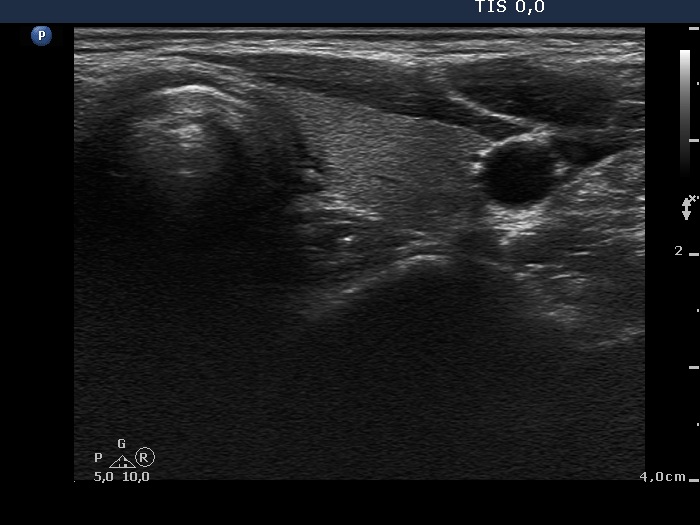

Differential diagnostic of thyroid cysts - Case 10. (ultrasonographic picture 5)

Left lobe, horizontal view. This lobe is intact.